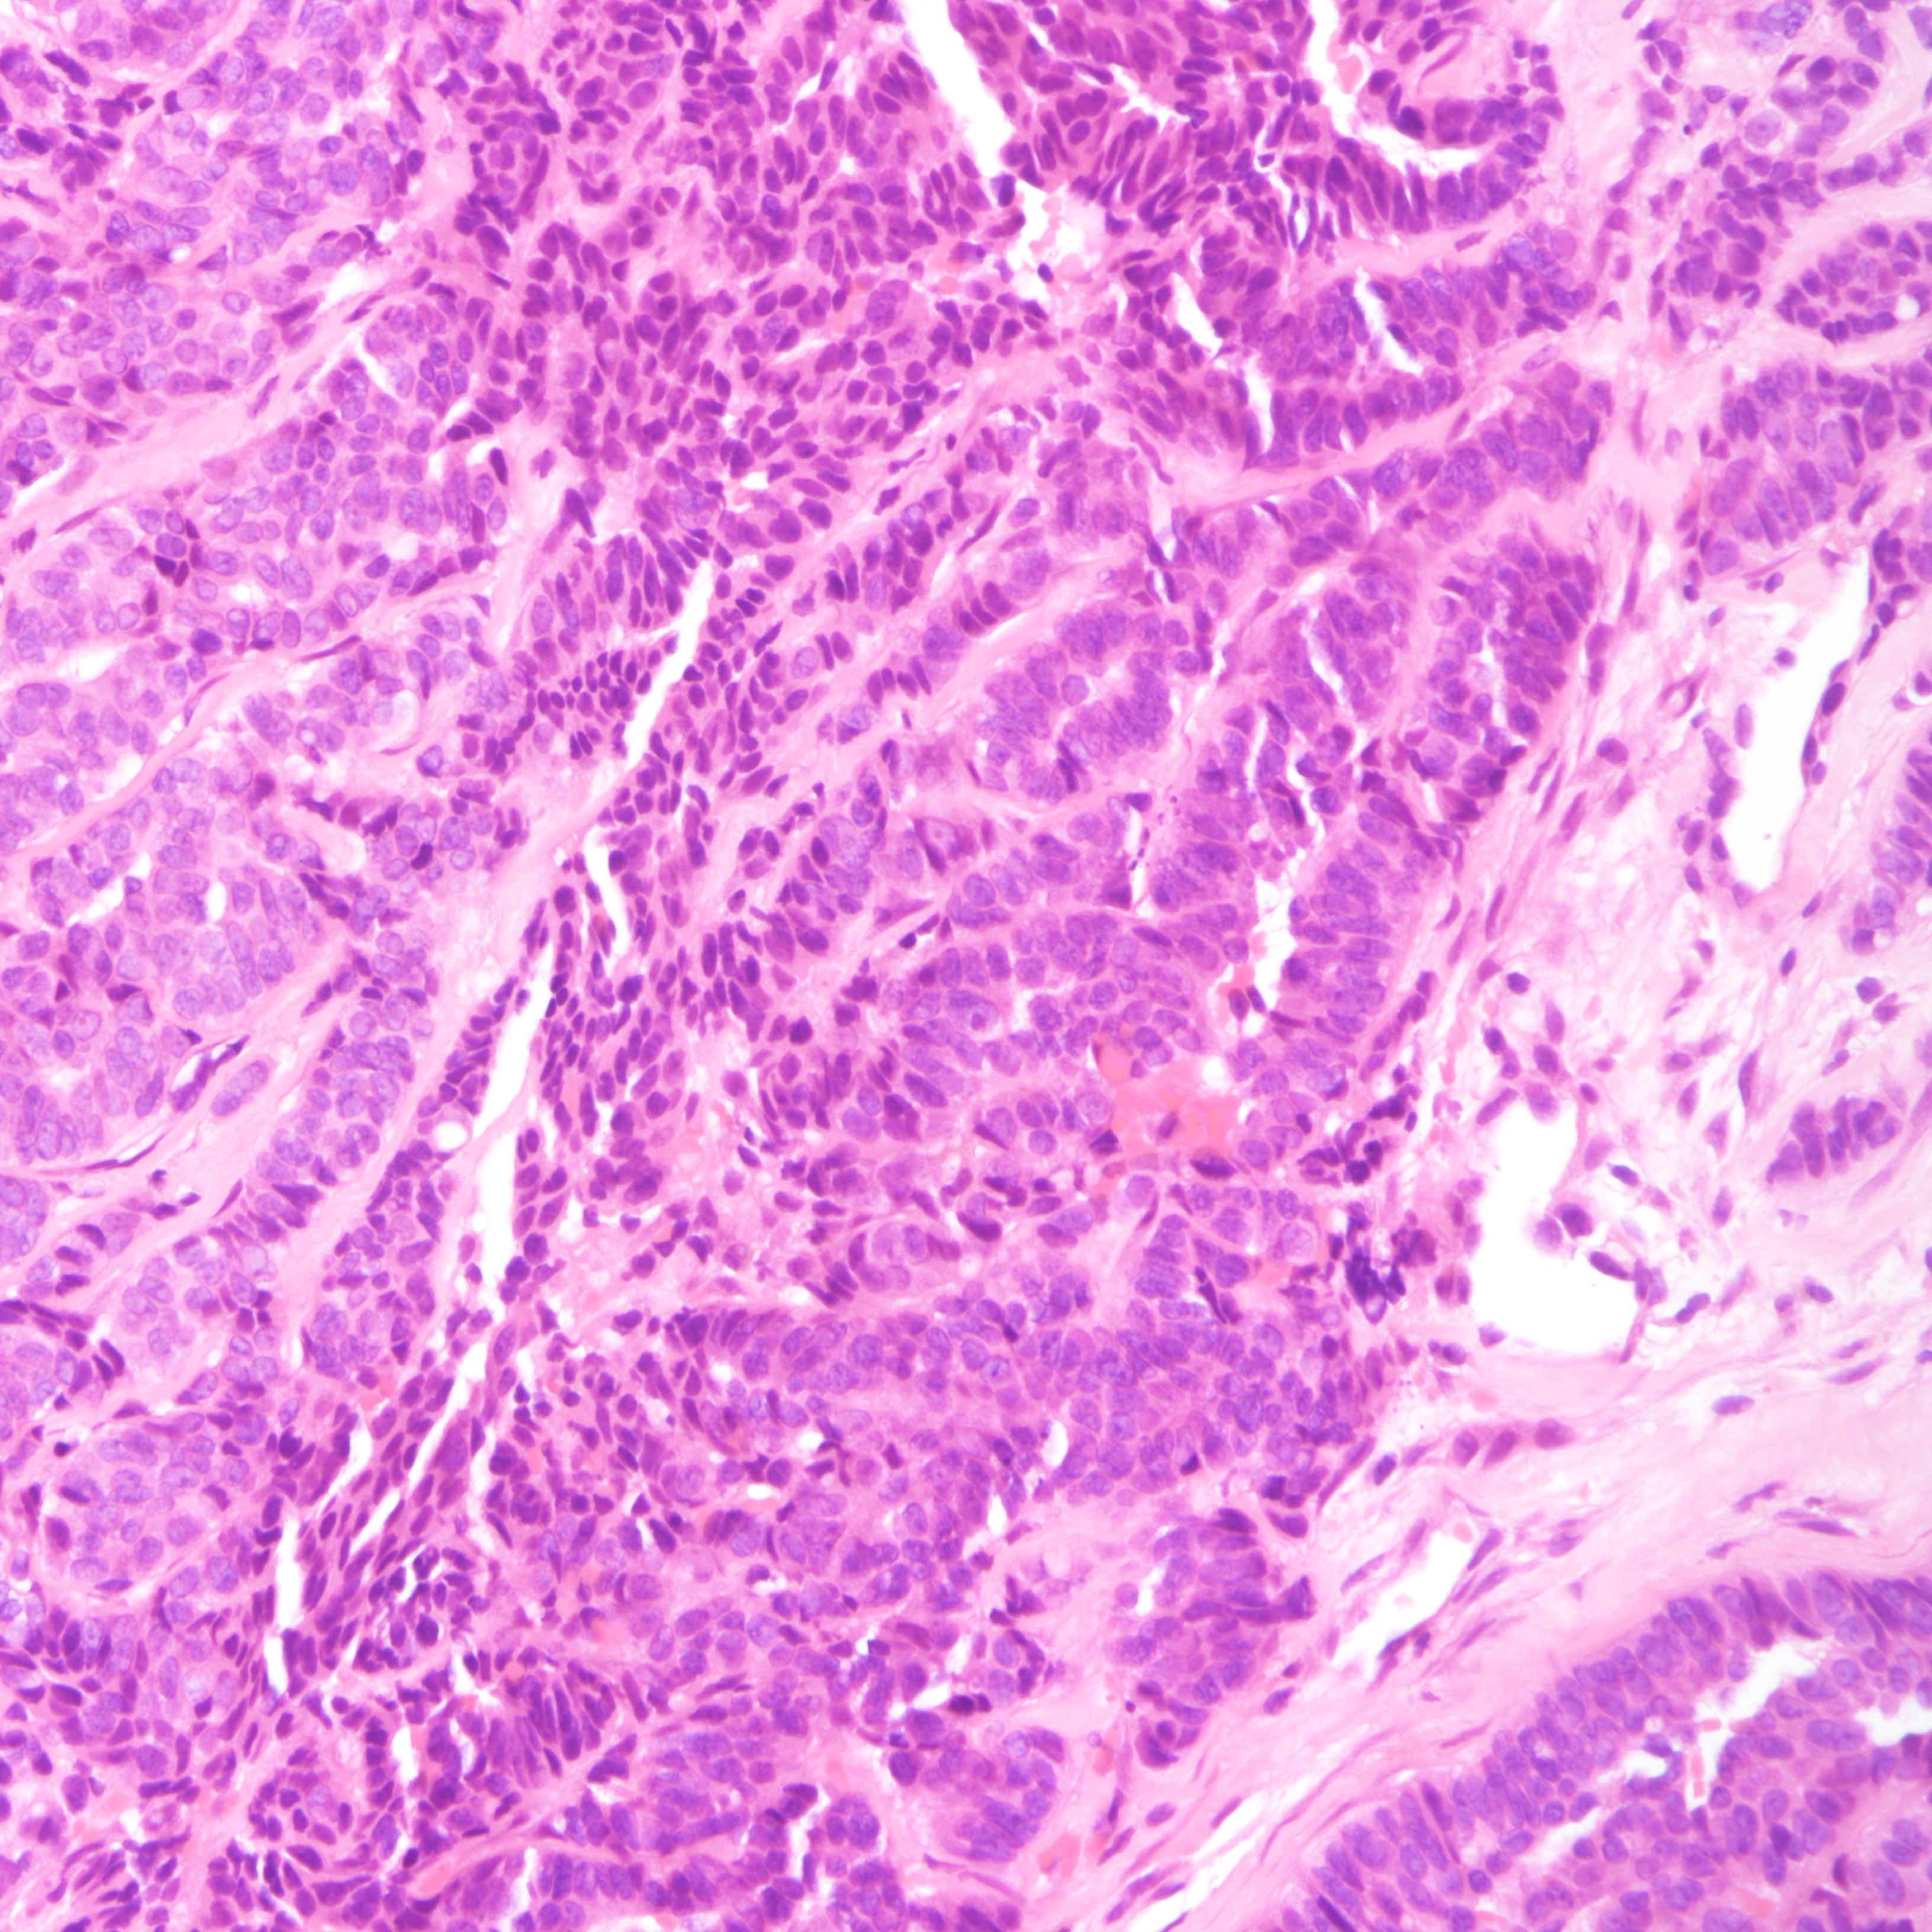

Microscopic (histologic) description

- Small cell carcinoma:

- Infiltrative growth pattern

- Crush artifact frequent

- Necrosis and lymphovascular invasion common

- Tumor cells densely packed with ill defined cell borders

- High N/C ratio with scanty cytoplasm

- Small dark hyperchromatic nuclei and inconspicuous nucleoli

- Mitotic count high

- Associated with proliferative changes, in situ carcinomas and invasive carcinomas (Am J Surg Pathol 2000;24:1231)

- In situ small cell carcinoma present in 5 out of 9 cases in a case series

- In situ / invasive ductal, lobular and squamous neoplastic components occasionally identified

- Infiltrative growth pattern

- Large cell carcinoma:

- High grade features (frequent necrosis, lymphovascular invasion and mitosis) similar to small cell carcinoma

- Tumor cells have a larger amount of cytoplasm

- Chromatin pattern coarse with occasional distinct nucleoli

- Neuroendocrine carcinomas of the breast histologically indistinguishable from their counterparts of other primaries

Microscopic (histologic) images

Small cell carcinoma

Large cell carcinoma